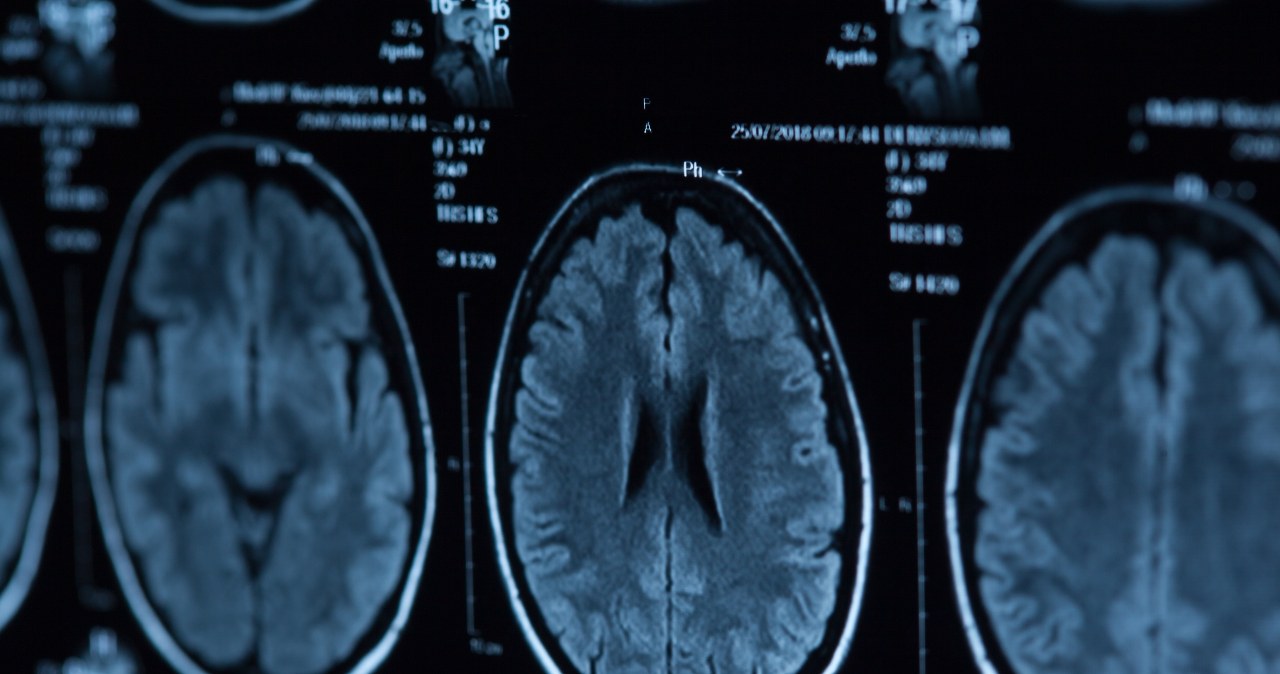

Badacze z uniwersytetów w Singapurze, USA i Kalifornii przeprowadzili badania, które ujawniły, że zwiększone prążkowie w mózgu może być związane z cechami psychopatycznymi. Wyniki tych badań zostały potwierdzone zarówno u mężczyzn, jak i kobiet, co stanowi istotny krok naprzód w rozumieniu biologicznych podstaw psychopatii.

Psychopatia charakteryzuje się połączeniem egocentryzmu, chłodu emocjonalnego oraz braku empatii i skruchy. W niektórych przypadkach mogą się pojawiać również zachowania antyspołeczne lub przestępcze oraz agresywność i impulsywność. Nowe badania wykazały, że osoby z cechami psychopatycznymi mają prążkowie w mózgu większe o 10% w porównaniu do przeciętnych osób. Różnice w budowie mózgu stanowią biologiczne podstawy niektórych zachowań psychopatycznych.

Prążkowie, obszar w przedmózgowiu, odpowiada za motywację, podejmowanie decyzji i przetwarzanie nagród. Pomaga także koordynować działania motoryczne i odgrywa rolę w planowaniu oraz reagowaniu na bodźce. Mimo wcześniejszych sugestii dotyczących jego związku z psychopatią, dopiero teraz potwierdzono jego znaczenie na podstawie dowodów.

Zespół badawczy wykorzystał skany rezonansu magnetycznego 120 dorosłych osób w Stanach Zjednoczonych. Uczestnicy zostali również poddani ocenie za pomocą narzędzia Psychopathy Checklist-Revised, służącego do identyfikacji cech psychopatycznych. W próbie znaleziono 12 kobiet potwierdzając, że powiększone prążkowie występuje u obu płci.